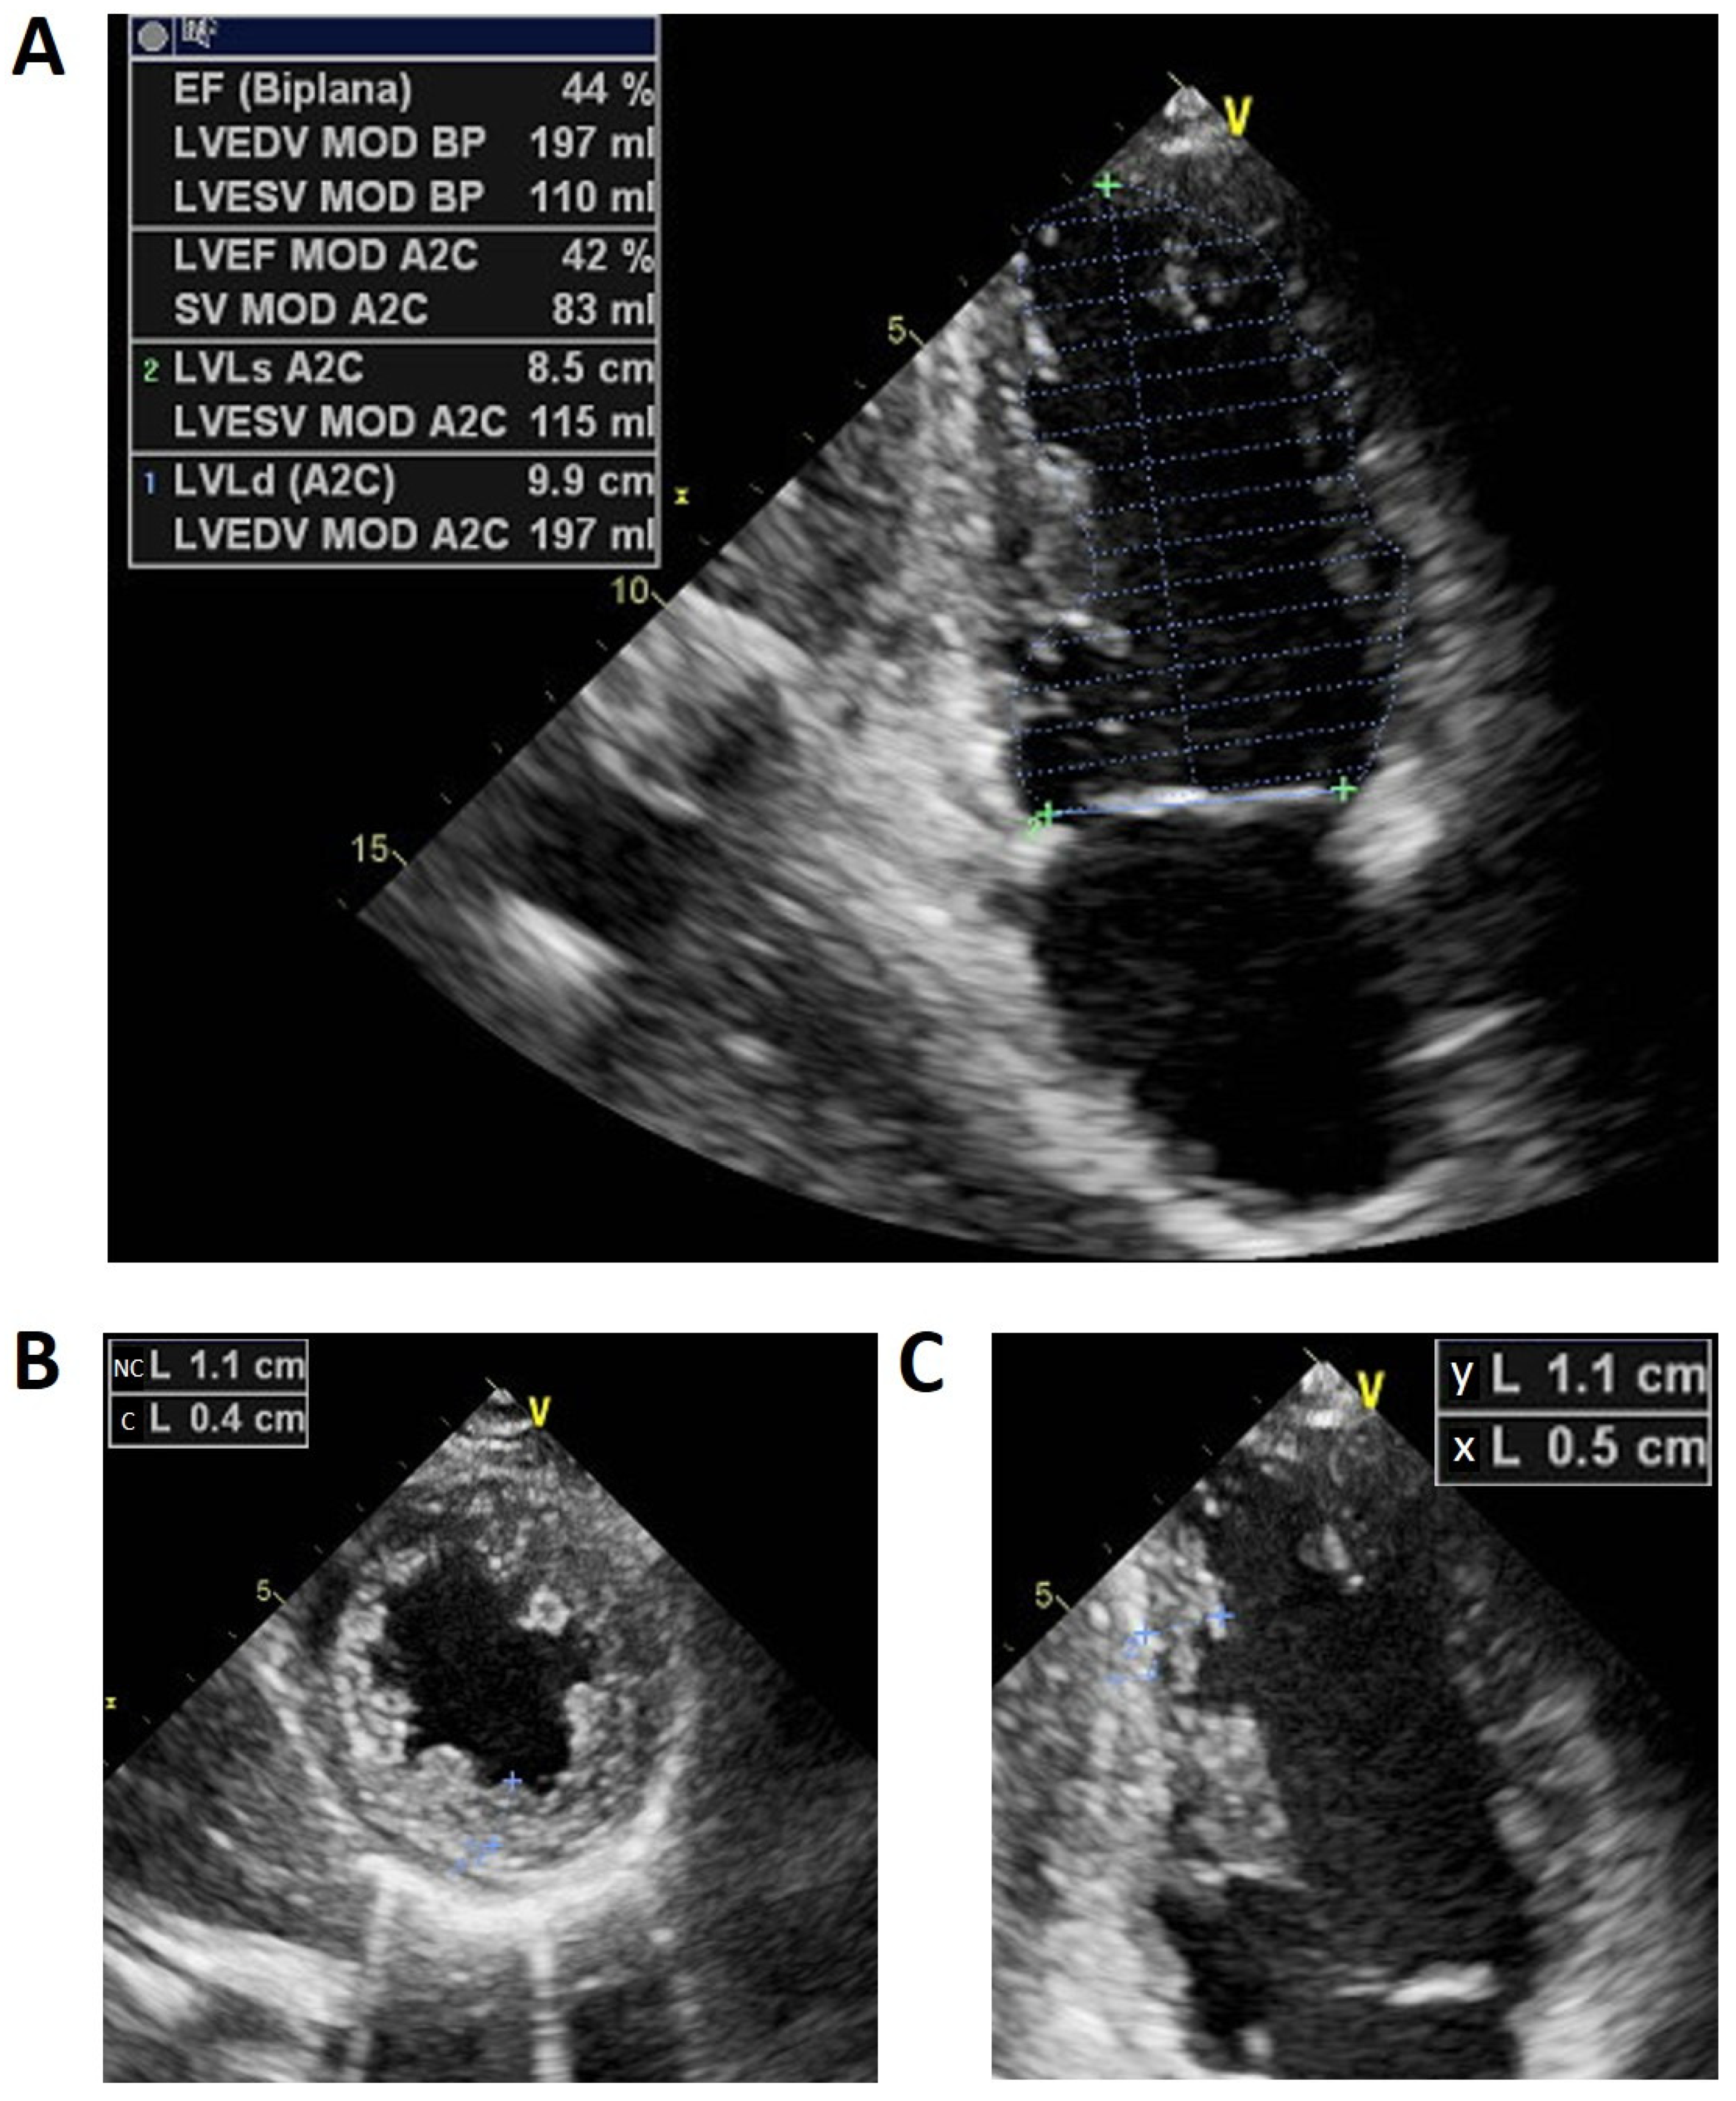

Echocardiographic examination repeated in our facility in the proband demonstrated a dilated left ventricle and a suspicion for left ventricular noncompaction (Figure 1). Incomplete left bundle branch block (LBBB) was seen on the electrocardiogram (ECG) (Figure 2).

Figure 1.

(A) Apical two-chamber view showing left ventricle (LV) dilatation (end-diastolic volume indexed 105 mL/m2 and end-systolic volume indexed 58 mL/m2), with a reduced ejection fraction (EF) (44%, biplane). (B) Parasternal short axis of LV during the systole phase showing a compact epicardial layer (C) and noncompacted endocardial layer (NC) mainly in the mid apical inferior and inferolateral left ventricle with prominent trabeculations and a maximal end systolic NC/C trabecular ratio > 2 (criteria reference: [15]). (C) Ratio of the distance from the epicardial surface to the trough of the trabecular recess (X) to the distance from the epicardial surface to the peak of the trabeculation (Y) with a ratio ≤0.5.